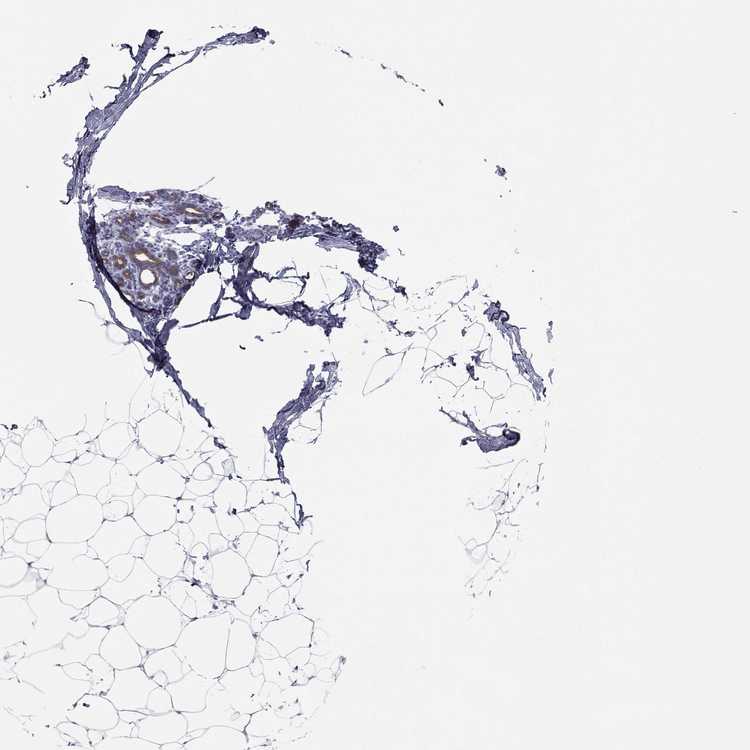

BREAST - Antibody stainingi

Antibody staining in the annotated cell types in the current human tissue is reported as not detected, low, medium, or high, based on conventional immunohistochemistry profiling in selected tissues. This score is based on the combination of the staining intensity and fraction of stained cells.

Each image is clickable and will lead to virtual microscopy that enables deeper exploration of all samples and also displays staining intensity scores, fraction scores and subcellular localization as well as patient and tissue information for each sample.

Antibody HPA041724Antibody HPA043539Antibody HPA076510

Adipocytes Not detectedNot detectedNot detected

Glandular cells LowMediumLow

Myoepithelial cells Not detectedNot detectedNot detected